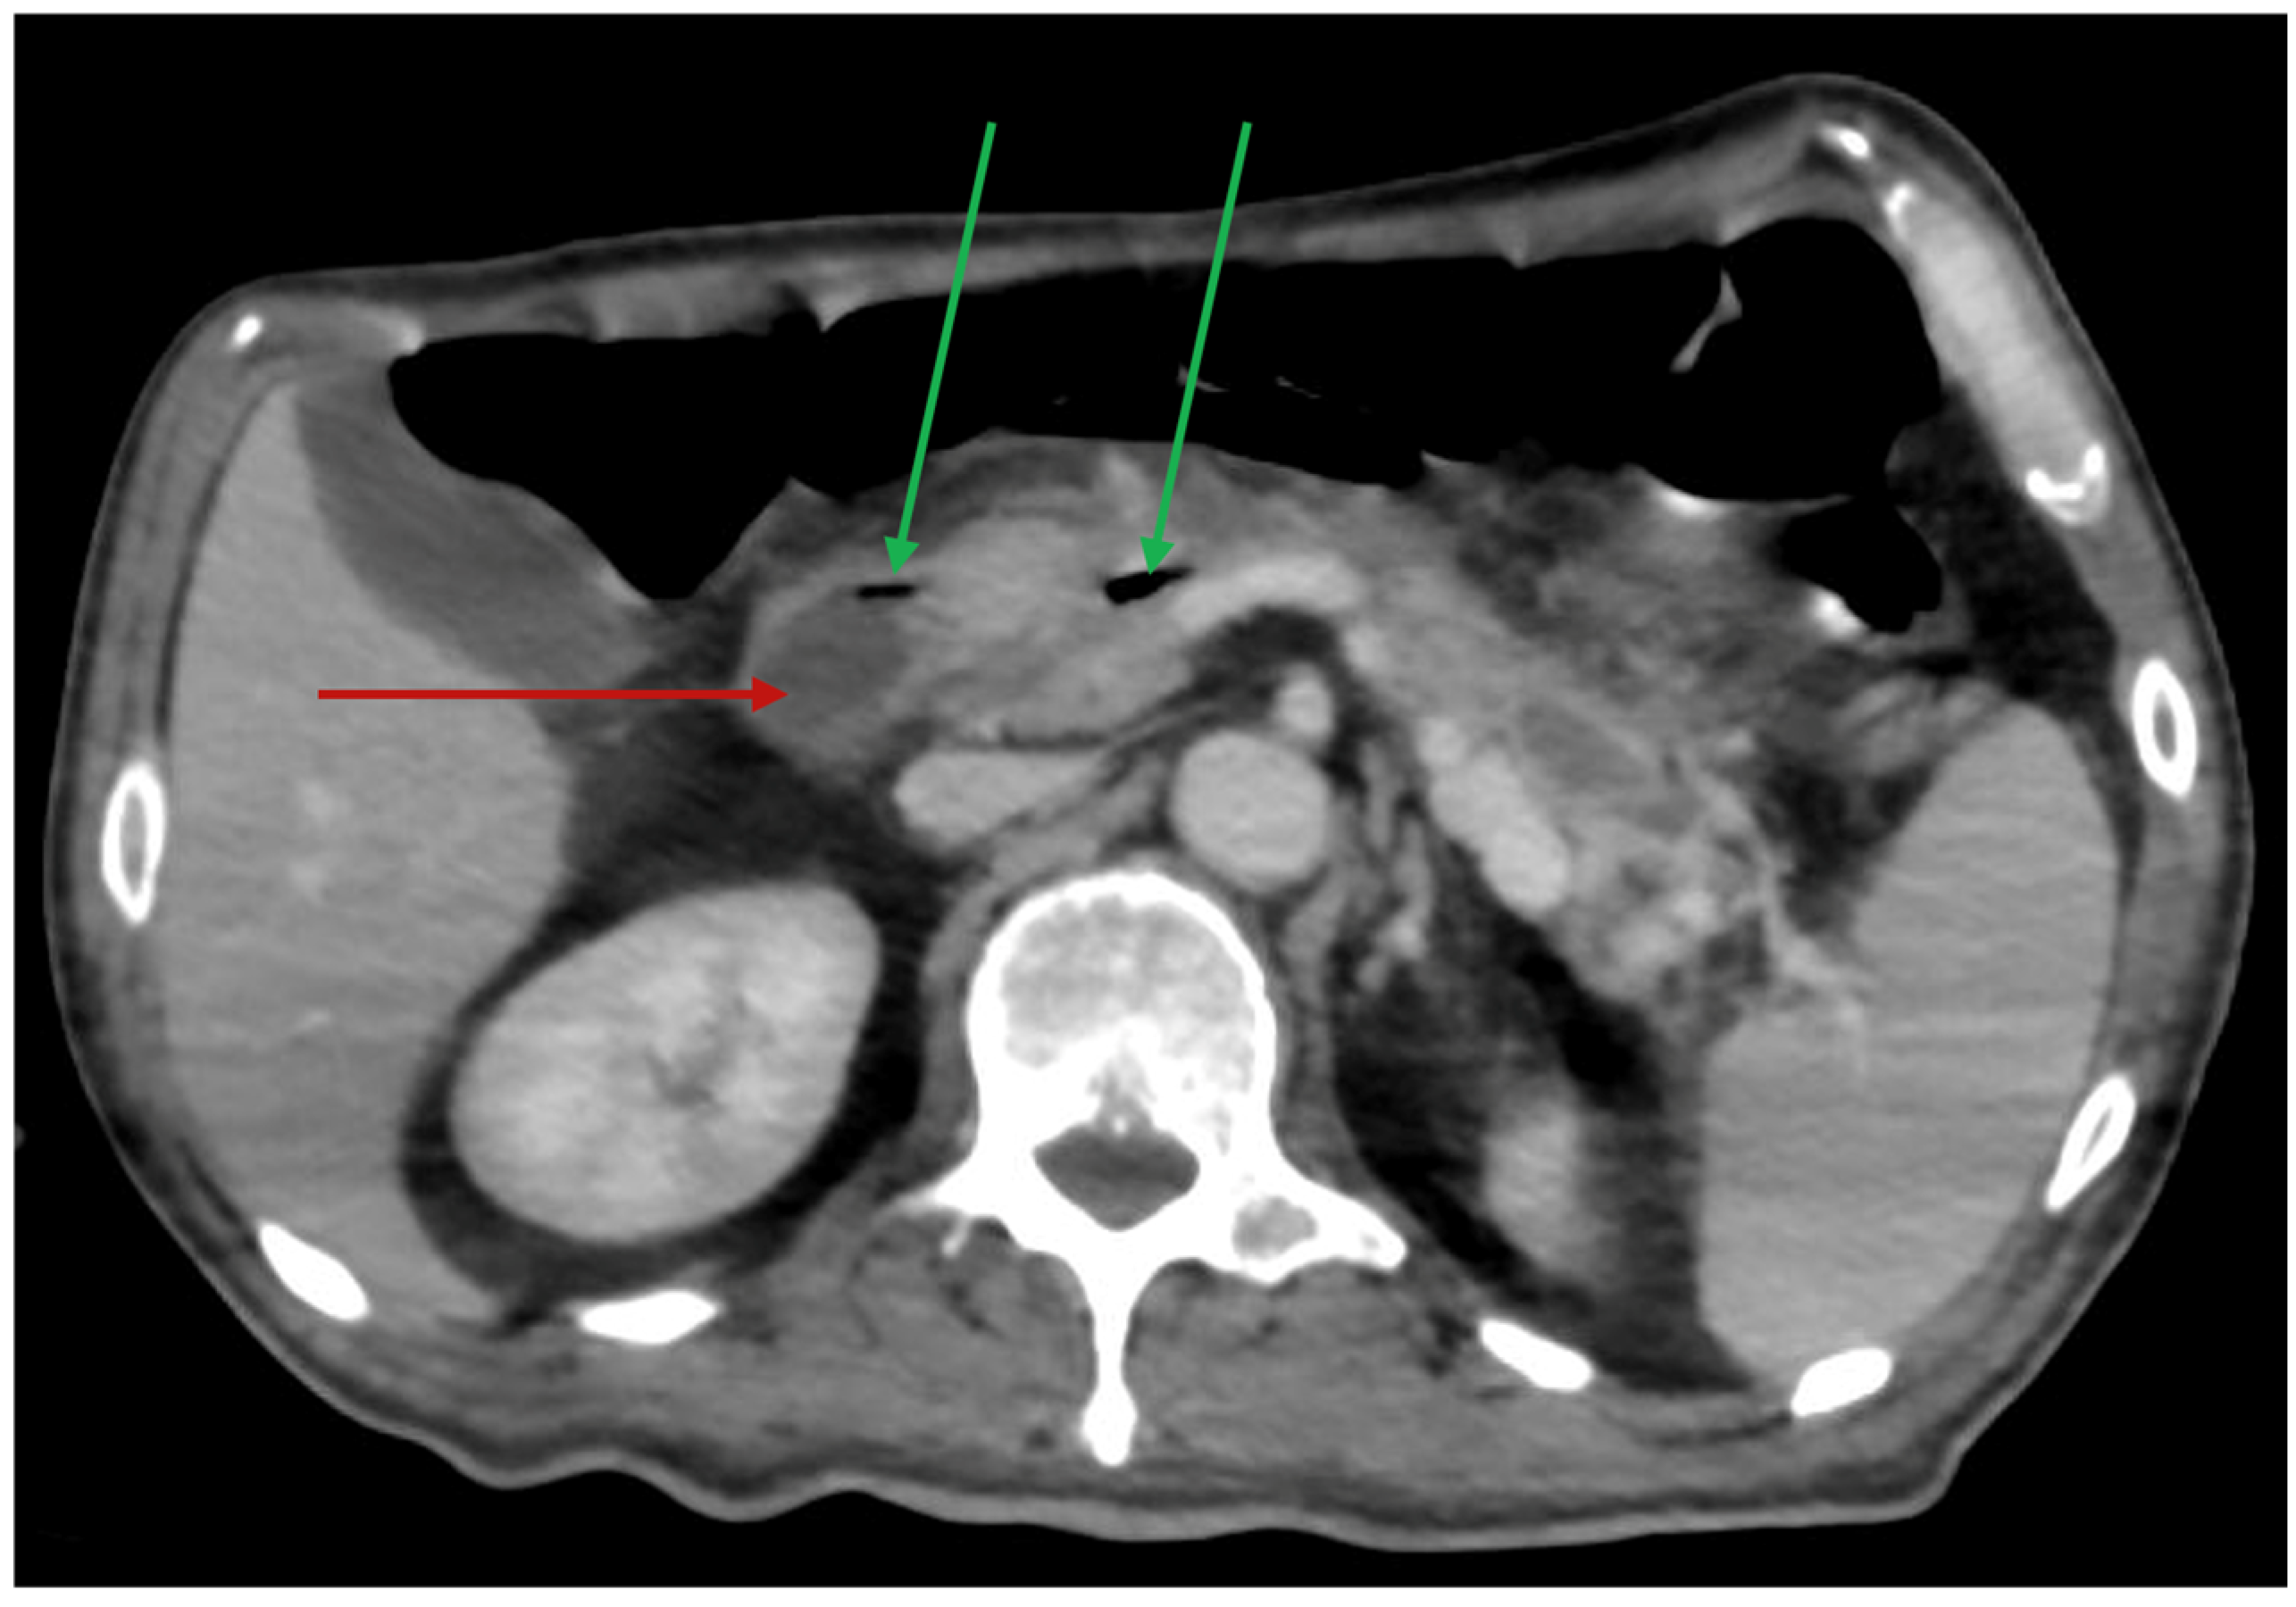

2.2.2. Admission and Clinical Deterioration

2.2.3. Isolation of Acinetobacter baumannii and Eravacycline Therapy